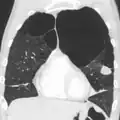

Lungs affected by COPD

Section of a lung showing centrilobular emphysema, with enlarged airspaces in the centre of a lobule usually caused by smoking and a major feature of COPD